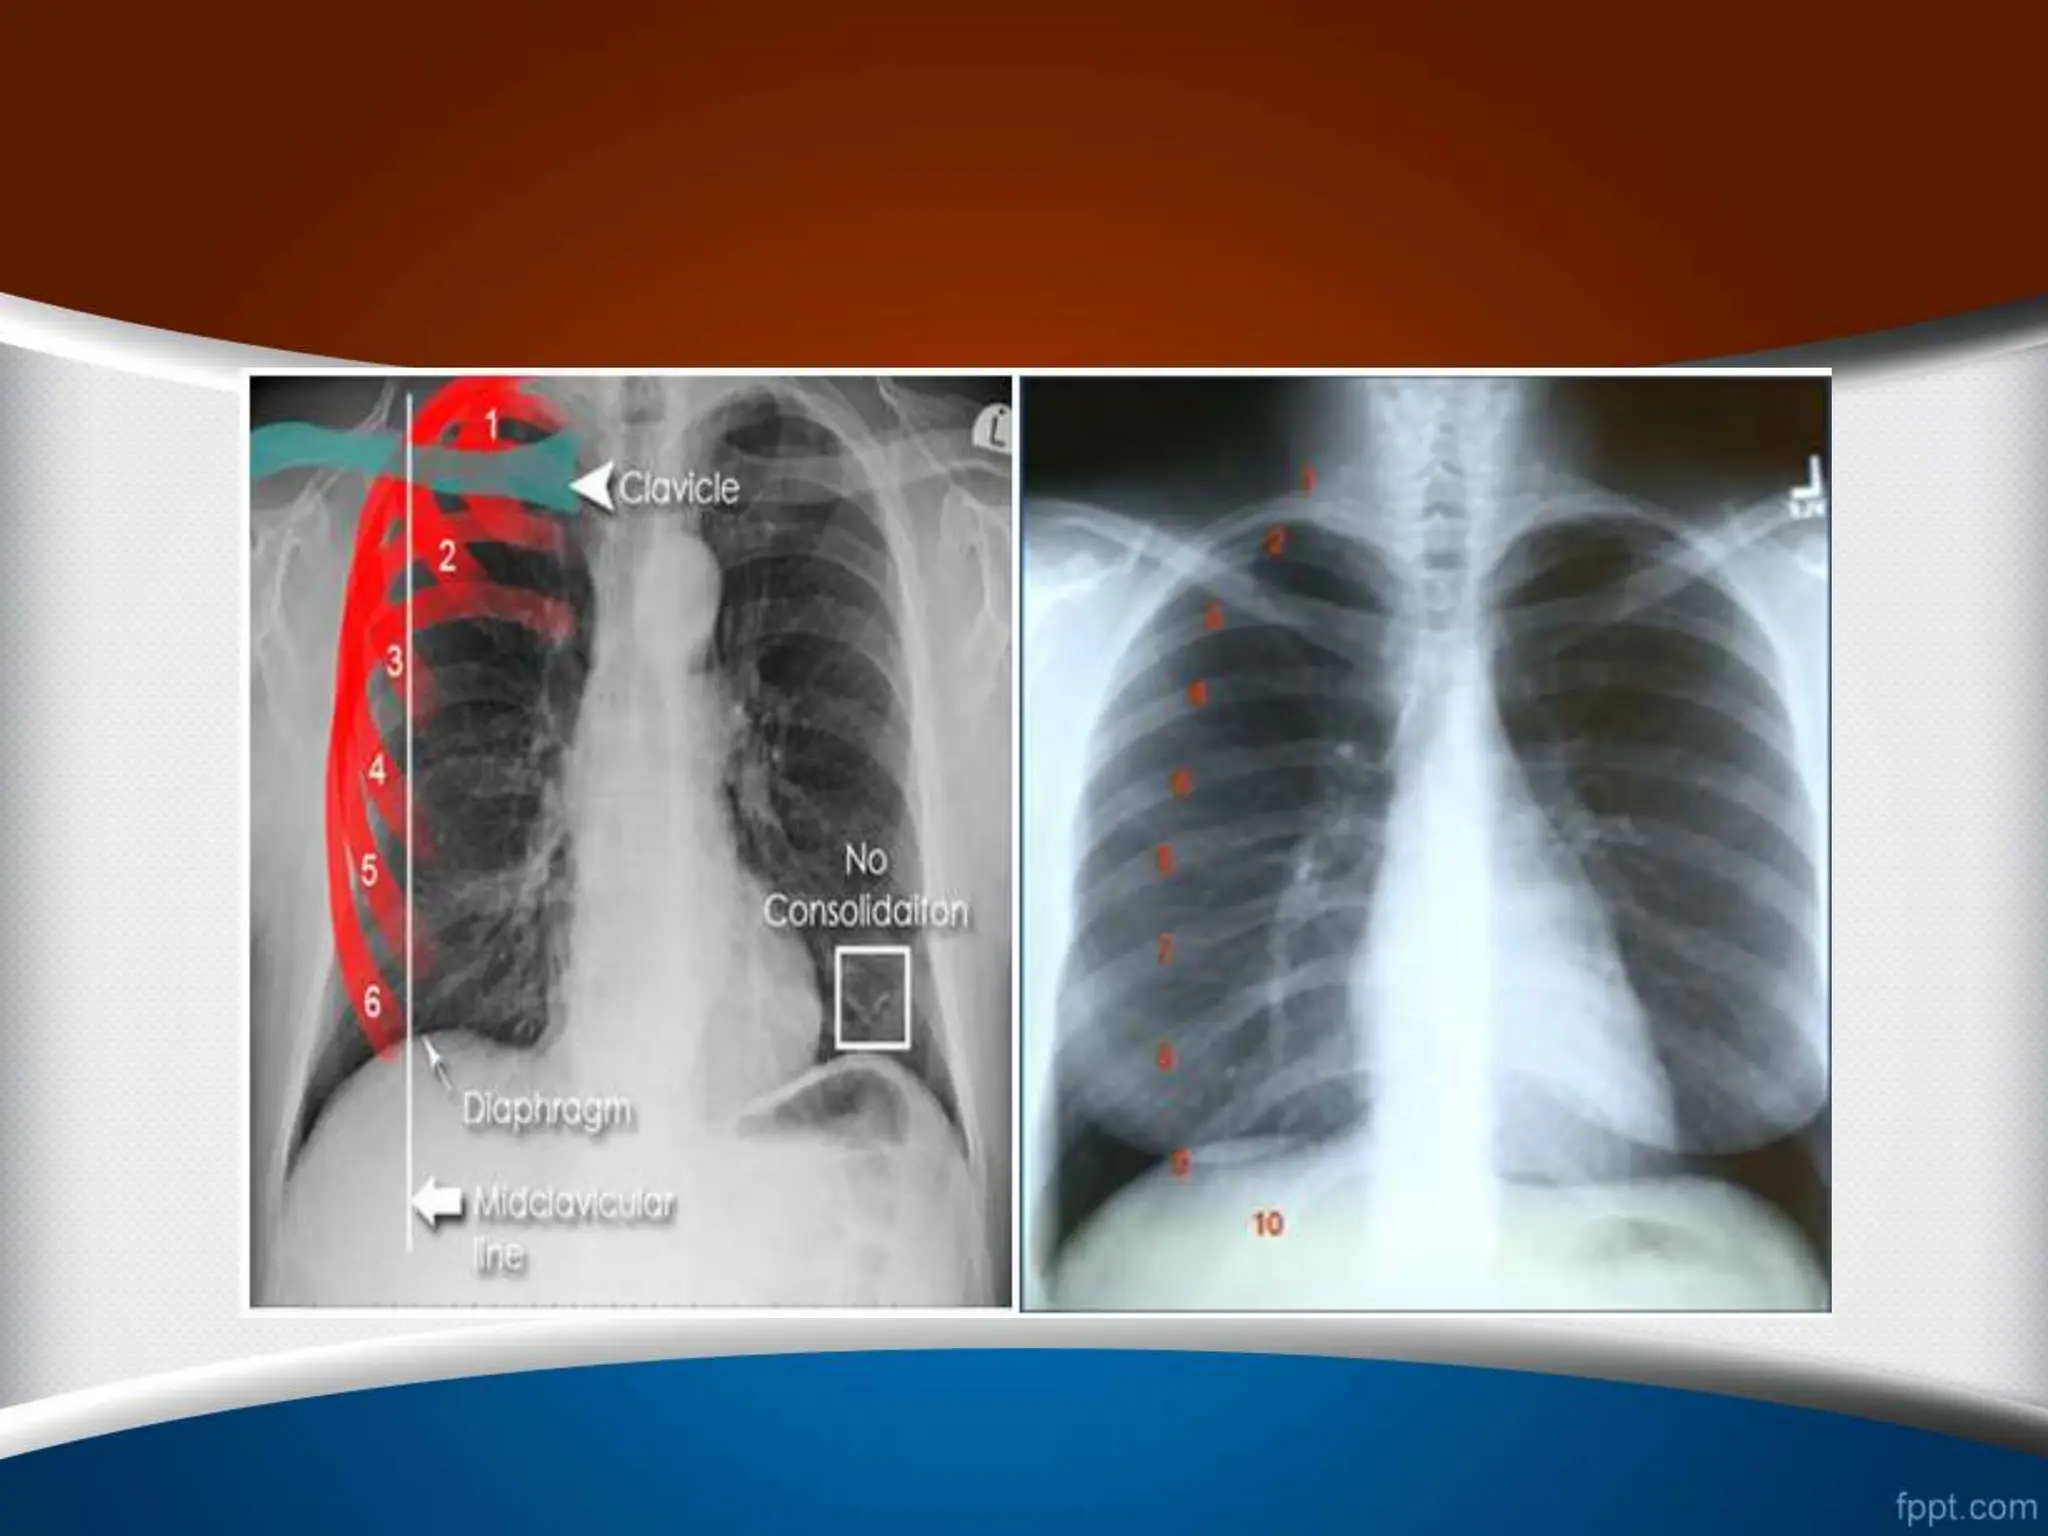

‫دم‬ ‫میزان‬

1

-

‫مشاهده‬

9

‫تا‬

12

‫یا‬ ‫خلفی‬ ‫دنده‬

6

‫در‬ ‫قدامی‬ ‫دنده‬

CXR

‫فرونتال‬

PA

‫میدکالویکول‬ ‫خط‬ ‫در‬

.

•

2

‫زاویه‬ ‫از‬ ‫اگر‬

‫خط‬ ‫کاردیوفرنیک‬ ‫به‬ ‫کوستوفرنیک‬ ‫ی‬

‫ی‬

‫فاص‬ ‫باشد‬ ‫شده‬ ‫انجام‬ ‫عمیق‬ ‫دم‬ ‫که‬ ‫صورتی‬ ‫در‬ ‫بکشیم‬

‫بین‬ ‫له‬

‫از‬ ‫بیشتر‬ ‫باید‬ ‫دیافراگم‬ ‫و‬ ‫خط‬ ‫این‬

1.5

‫سانتی‬

‫باشد‬ ‫متر‬

3

‫باشد‬ ‫شده‬ ‫پوشیده‬ ‫دیافراگم‬ ‫توسط‬ ‫قلب‬ ‫کناره‬